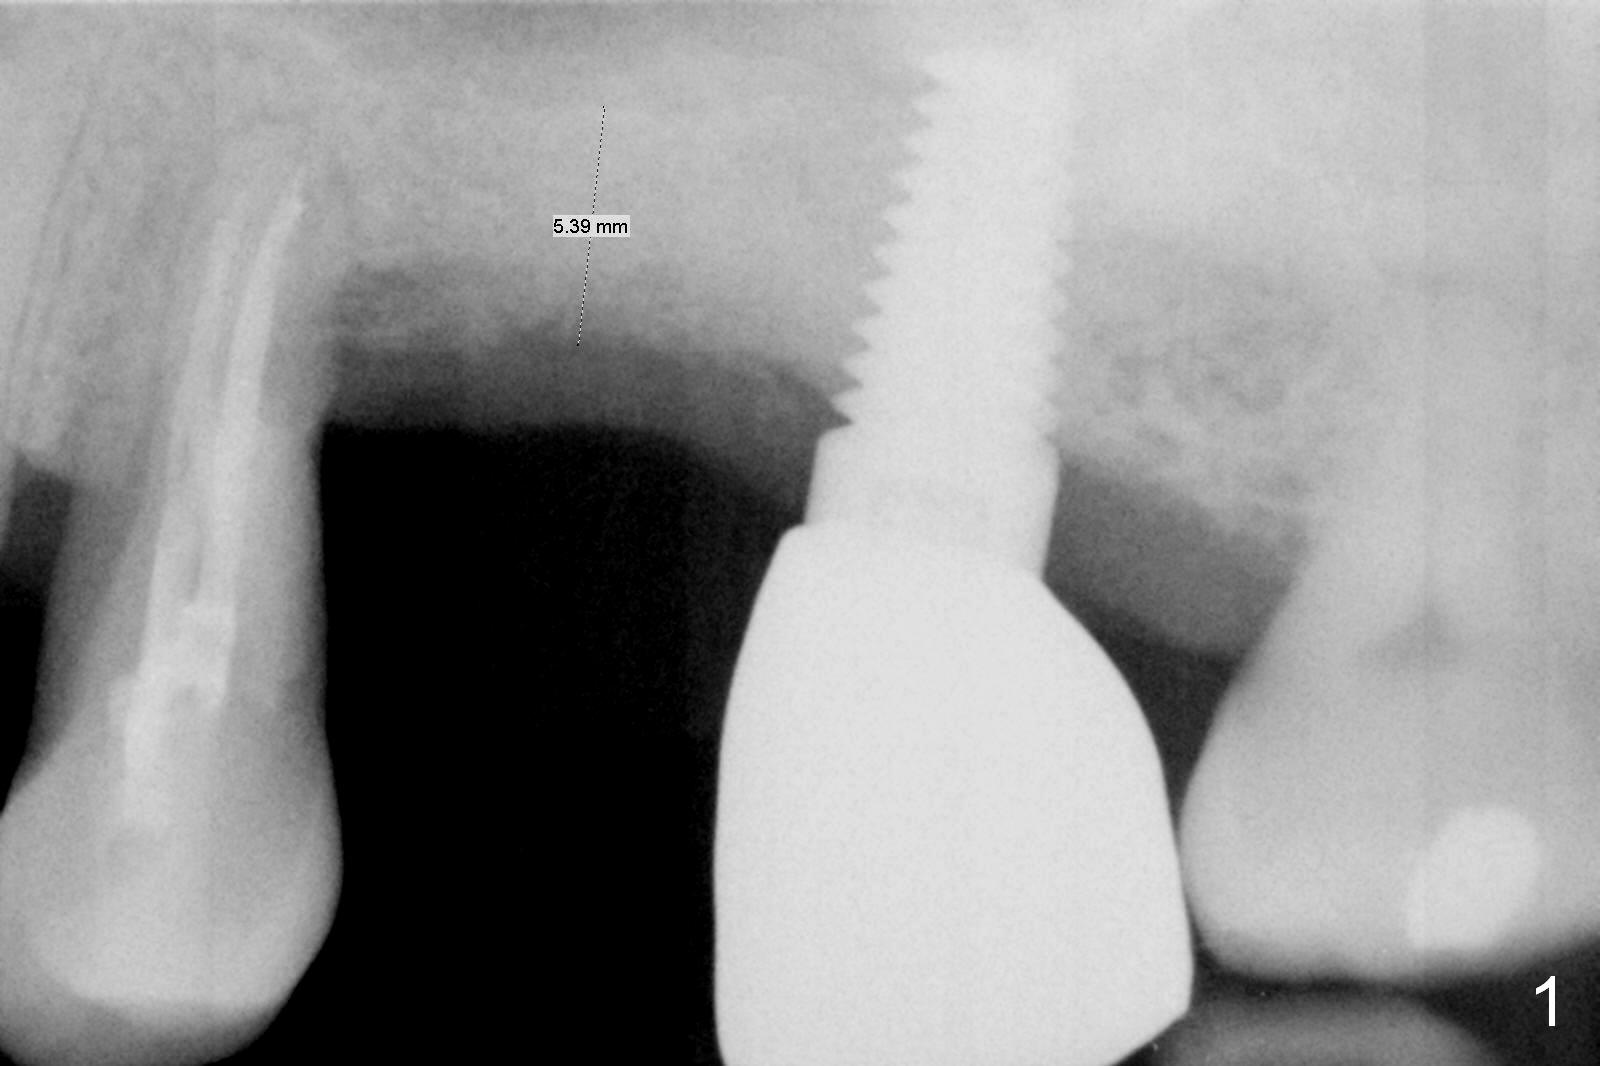

Four months post bone graft, the bone height at #14 is ~ 5 mm (Fig.1). After osteotomy for 4 mm with 4.3 mm Magic Drill (hard bone), Magic Sinus Lifter is used for sinus lift for ~ 8 mm without sinus membrane perforation. Perforation occurs with pulsating hemorrhage after sinus lift with allograft (.5-1 mm, mixed with Metronidazole). Collagen plug is used to repair the perforation before placing a short (5x7 mm) IBS implant with ~ 25 Ncm (Fig.2). After placing a 6.5x5.7(3) mm abutment, allograft is placed around the most coronal exposed implant thread (^). Acrylic is applied over the abutment for wound protection. There is mild nasal hemorrhage for 2 days postop. To prevent and treat sinus membrane perforation, PRF will be routine prepared preop for future cases. New bone forms apically and coronally 4.5 months postop (Fig.3,4 ^). A new temporary crown is fabricated so that it can undergo progressive loading for a few months before final impression. The definitive restoration is delivered 7.5 months postop (Fig.5). The bone density apical to the implant becomes apparently denser nearly 5 months post cementation (Fig.6). The bone density in the crest increases 2 years post cementation (Fig.7 *).